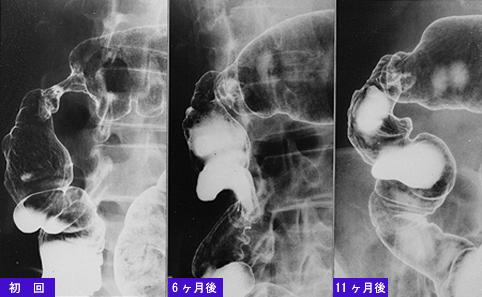

A case of colonic tuberuculosis which was almost completely cured by antituberuculosis medicine.

Inflammatory or ulcerative disease / lesions/tuberculosis

Large intestine(Colon)/More than one of the above

X-ray